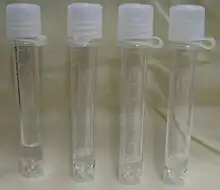

Cerebrospinal fluid (CSF) is a clear, colorless body fluid found within the tissue that surrounds the brain and spinal cord of all vertebrates.

A sample of CSF can be taken from around the spinal cord via lumbar puncture. This can be used to test the intracranial pressure, as well as indicate diseases including infections of the brain or the surrounding meninges.

Testing often includes observing the colour of the fluid, measuring CSF pressure, and counting and identifying white and red blood cells within the fluid; measuring protein and glucose levels; and culturing the fluid.[32][34] The presence of red blood cells and xanthochromia may indicate subarachnoid hemorrhage; whereas central nervous system infections such as meningitis, may be indicated by elevated white blood cell levels.[34] A CSF culture may yield the microorganism that has caused the infection,[32] or PCR may be used to identify a viral cause.[34] Investigations to the total type and nature of proteins reveal point to specific diseases, including multiple sclerosis, paraneoplastic syndromes, systemic lupus erythematosus, neurosarcoidosis, cerebral angiitis;[1] and specific antibodies such as aquaporin-4 may be tested for to assist in the diagnosis of autoimmune conditions.[1] A lumbar puncture that drains CSF may also be used as part of treatment for some conditions, including idiopathic intracranial hypertension and normal pressure hydrocephalus.[1]